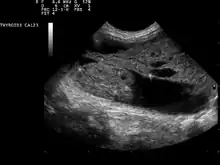

Ultrasound artifacts showing a "comet tail" from a colloid nodule indicate a benign nodule

Ultrasound imaging is useful as the first-line, non-invasive investigation in determining the size, texture, position, and vascularity of a nodule, accessing lymph nodes metastasis in the neck, and for guiding fine needle aspiration cytology (FNAC) or biopsy. Ultrasonographic findings will also guide the indication to biopsy and the long term follow-up.[10] High frequency transducer (7–12 MHz) is used to scan the thyroid nodule, while taking cross-sectional and longitudinal sections during scan. Suspicious findings in a nodule are hypoechoic, ill-defined margins, absence of peripheral halo or irregular margin, fine, punctate microcalcifications, presence of solid nodule, high levels of irregular blood flow within the nodule[11] or "taller-than-wide sign" (anterior-posterior diameter is greater than transverse diameter of a nodule). Features of benign lesion are: hyperechoic, having coarse, dysmorphic or curvilinear calcifications, comet tail artifact (reflection of a highly calcified object), absence of blood flow in the nodule, and presence of cystic (fluid-filled) nodule. However, the presence of solitary or multiple nodules is not a good predictor of malignancy. Malignancy is only diagnosed when ultrasound findings and FNAC report are suggestive of malignancy.[11] The TI-RADS (Thyroid Imaging Reporting and Data Systems) are sonographic classification systems which describe the suspicious findings of thyroid nodules.[12] It was first proposed by Horvath et al.,[13] based on the BI-RADS (Breast Imaging Reporting and Data System) concept. Several systems were subsequently proposed and adopted by international scientific societies. Their main aims are to characterize the risk of malignancy of nodules to better select nodules to submit to fine-needle aspiration cytology.[14] TI-RADS developed by the American College of Radiology (ACR) guides clinicians in deciding which nodules require FNAC and in planning follow-up. Various online tools have been developed to assist in applying these criteria to clinical practice. [15]